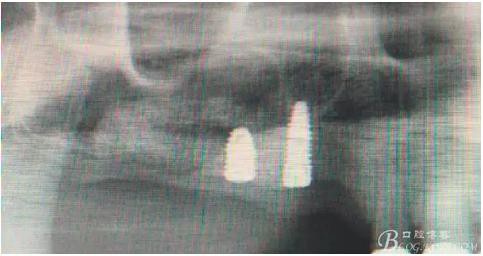

14,15牙位植入兩顆植體,6,7牙位骨高度嚴(yán)重不足,且骨密度低,無法給植體提供良好的初期穩(wěn)定性,需二期植入。13牙位骨寬度不足,沒有植骨、植植體,修復(fù)時用后面4顆連冠加一顆3的游離臂是沒有問題的。當(dāng)然這里我們不去討論這個方法的合理性,我們今天的話題是改良式外提升技術(shù)的應(yīng)用。

術(shù)后40天X光片。